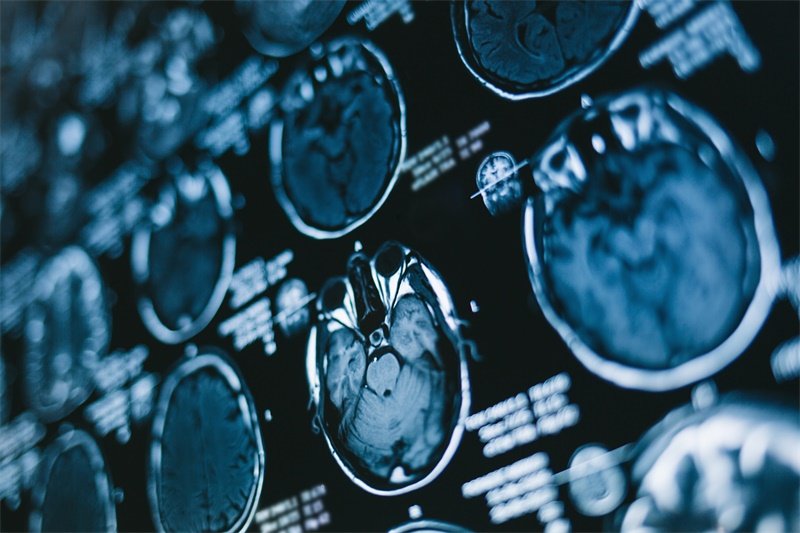

丘脑作为大脑深部的“信息中转站”,负责整合感觉、运动及意识信号。当影像学报告提示“左颞顶枕丘脑占位”时,患者常陷入对未知病变的焦虑。这类占位病变性质复杂,既可能是低风险的良性肿瘤,也可能是侵袭性的胶质瘤,其症状隐匿且易被误诊为视力下降或偏头痛。早期精准鉴别病变性质,对制定治疗方案、保护神经功能至关重要。

•MRI增强扫描是金标准,可区分肿瘤边界、水肿带及出血灶。